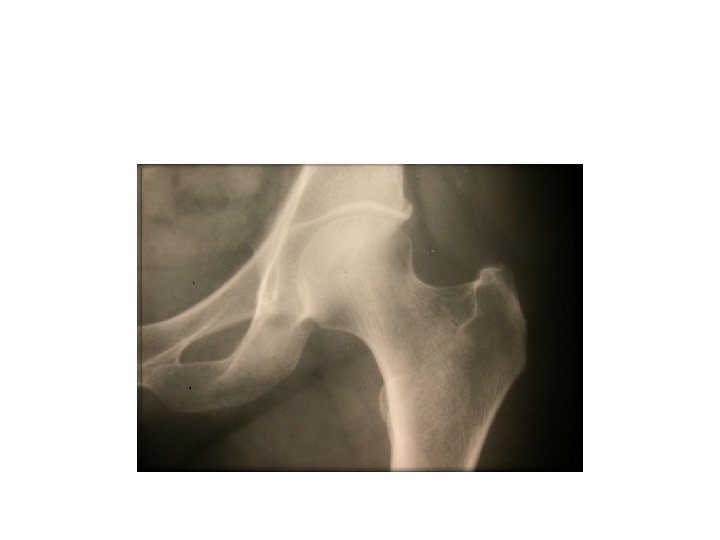

SEMIOLOGIE DE LA HANCHE J-P ESCHARD • Anatomie Articulation profonde Articulation très emboîtée mobilité

SEMIOLOGIE DE LA HANCHE J-P ESCHARD • Anatomie Articulation profonde Articulation très emboîtée mobilité réduite